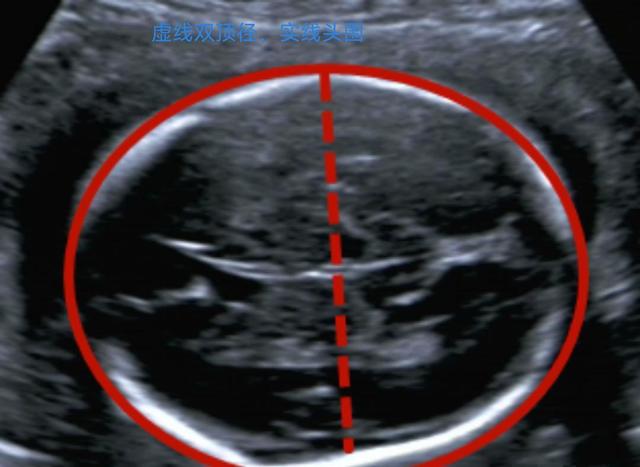

什么时候做大排畸最好?医生说一般在怀孕20周到24周做,这时候宝宝各个器官基本发育好了,超声检查照出来的图像也更清楚,要是做得太早,有些器官还没长全乎;太晚了宝宝长大,骨头钙化了,超声穿不过去,就查不准了。

检查内容可全乎了,从宝宝脑袋到脚趾都得“扫”一遍,看看有没有结构发育不正常的地方,像脑袋、心脏、胳膊腿儿这些地方有没有先天毛病,好多人觉得查一次没事就万事大吉了,其实也不全对,大排畸只是筛查,不能保证宝宝绝对健康,但能早点发现一些严重问题。